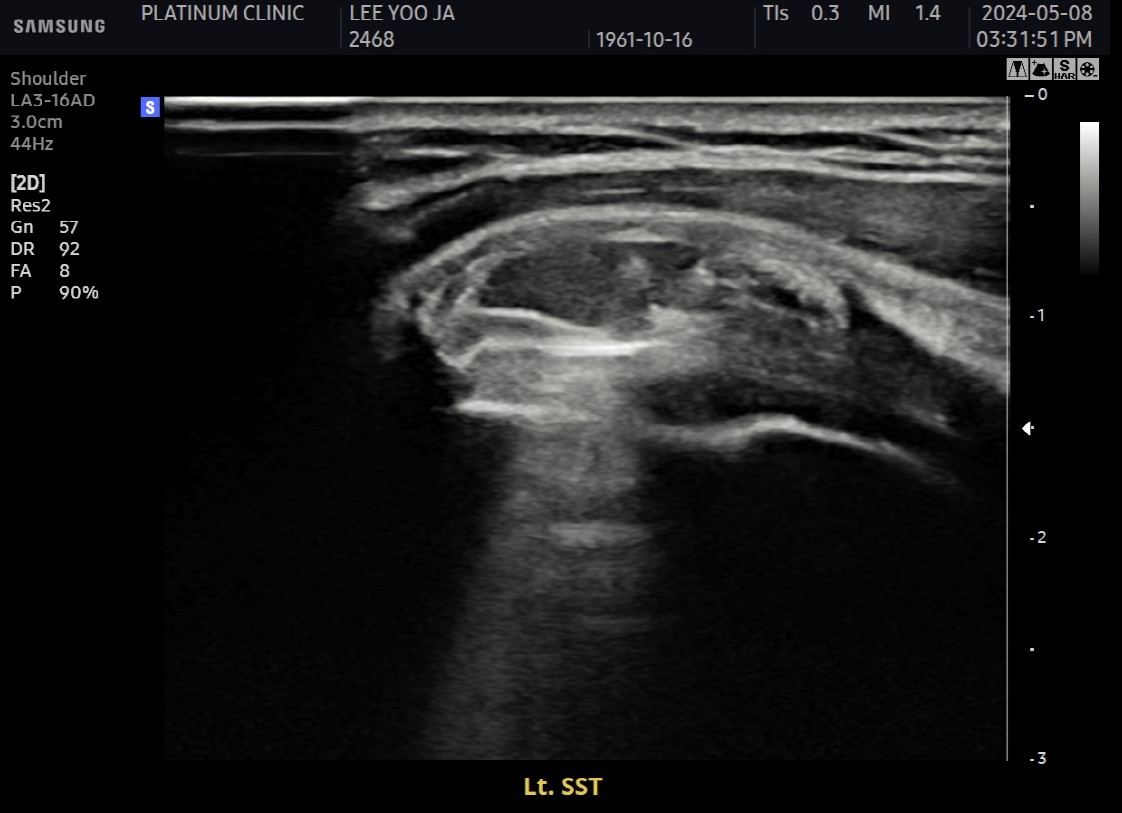

Step 4: 흡입

분쇄된 석회를 강력하게 흡입합니다.

분쇄 조각들이 빨려 나옴

흡입된 석회를 눈으로 확인 가능

큰 조각부터 작은 가루까지 제거

Step 5: 세척

인대 사이사이에 남은 미세 석회를 세척합니다.

생리식염수 주입

인대 조직 사이 잔여 석회 씻어냄

깨끗해질 때까지 반복

Step 6: 최종 확인 및 마무리

초음파와 X-ray로 석회 제거 확인 후 마무리합니다.

초음파: 석회 부위 확인

X-ray: 석회 완전 제거 확인